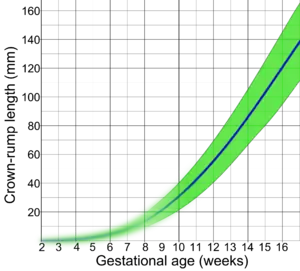

Following are diagrams for estimating gestational age from obstetric ultrasound, by various target parameters:

By gestational sac diameter By crown-rump length (CRL)